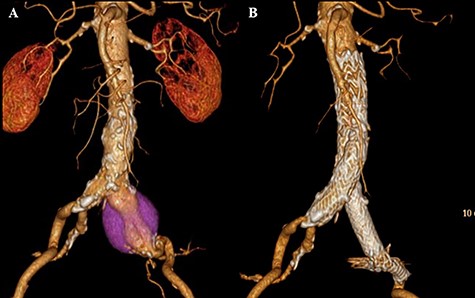

A 76-year-old man was incidentally diagnosed with a left CIAA by abdominal ultrasonography, with computed tomography (CT) demonstrating a left CIAA measuring 4.5 cm in diameter (Fig. 1A). The patient was referred to our hospital for surgical treatment. He had a medical history of liver cirrhosis and traumatic abdominal injury. Thus, he underwent EVAR using a GORE EXCLUDER AAA Endoprosthesis to embolize the left internal iliac artery. The postoperative course was uneventful, and postoperative CT showed no endoleak (Fig. 1B). Follow-up CT scans at 6-month, 1-year and 2-year intervals post-EVAR revealed a reduction in the size of the aneurysmal sac. However, the 3-year interval CT demonstrated an increase in the sac size (Fig. 2A). Contrast-enhanced CT and angiography revealed no endoleak but showed a dilatation of the CIAA. Therefore, the patient underwent open aortic repair of the CIAA.

CT scan showing left CIAA (A). Contrast-enhanced CT demonstrating no endoleak after EVAR using a GORE EXCLUDER AAA Endoprosthesis to embolize the left internal iliac artery (B).